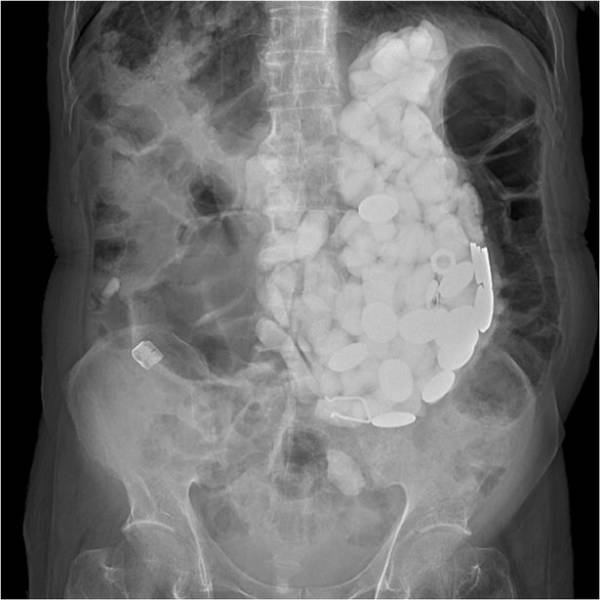

پزشکان سنگ، سر بطری و سکه را از بدن مردی که آن ها را برای درمان اضطرابش می خورد، بیرون کشیدند. مرد 54 ساله ای در بیمارستان بستری شده است و از درد شدید معده و باد کردگی رنج می برد. پزشکان مربوطه تعدادی از آزمایش ها را انجام دادند تا ببینند علت دردهای او چه چیزهایی می توانند باشند. آن ها متوجه شدند که وقتی شکم او را لمس می کنند چیزی شبیه سنگ های کوچک حس می کنند اما همین آزمایش نشان داد که یک جسمی بزرگ از اشیا، شکم بیمار را اشغال کرده است.

زمانی که یک توده حاوی ده ها شی خارجی پیدا شد، پزشکان به طور عجیبی تعجب کردند. مجموعه ای از سنگ ها، درپوش بطری و سکه ها به وزن 2 کیلوگرم را از معده اش بیرون کشیده شدند؛ این مورد بسیار غیر معمول، توسط دکتر پیونگ وا در ژورنال آمریکایی گزارش های پزشکی منتشر شد.

این مرد که گمان می رود اهل گویانگ - شمال پایتخت سیول و نزدیک مرز کره شمالی است - با یک معلولیت ذهنی به دنیا آمده است. در ابتدا جراحان سعی کردند اشیا را با استفاده از گاستروسکوپی بیرون بکشند، که در آن یک لوله باریک از طریق دهان وارد شکم می شود. در این میان، در بزرگسالان سالم، اشیا قورت داده شده و شامل استخوان ماهی و مرغ می شوند. دکتر چوئی نوشت:" هنگامی که اجسام خارجی از طریق مری عبور می کند، علائم مربوط به آن نادر است. " در این مورد، با وجود اینکه بیمار از استفراغ شکایت نکرده است، اما تعداد زیادی سکه در معده او باعث درد شکمی شده است."